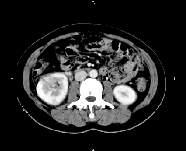

问题 女,27岁,寒战高热、尿频、尿痛3天,尿检:白细胞(+++),CT平扫及增强扫描如图所示,下列说法错误的是 ( )

选项 A、考虑为急性肾盂肾炎 B、考虑为慢性肾盂肾炎 C、增强后可见条片状密度减低区 D、左肾未见异常 E、右肾体积增大

答案 B